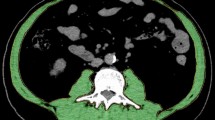

Patients (n = 3) whose CT quality was not suitable for analysis on ImageJ software due to artifact or a restricted field of view for waist circumference or skeletal muscle mass measurement were excluded. The measurement technique is detailed in a previously published article by Gomez et al. [11] and summarized in Fig. 1.

Measurement technique summarized in three steps. Step 1: after adjusting the image threshold between − 250 and + 1000, we click on the outer surface of the threshold-highlighted area with a wand tracing tool which delineates the abdominal perimeter (yellow contour in 1a). Step 2: the image returns to its original gray color after adjusting the threshold between − 250 and − 250 and we remove the yellow line by clicking on freehands selection tool. A stylus is then used to trace the outer muscle perimeter (arrow in 1b and 1c) for which measurement is obtained after making the threshold between − 29 and + 150. Step 3: the threshold is adjusted back between − 250 and − 250 then tracing of the inner muscle perimeter (arrowhead in 1c) is performed using the stylus. This measurement is also obtained after adjusting the threshold between − 29 and + 150

5-year-old boy with a history of prematurity and hepatoblastoma status post-liver transplantation presenting with abdominal pain and fever. He was found to have cholangitis and was admitted to ICU. The patient eventually died due to sepsis and multiorgan failure. His BMI was 15.96 (normal for age and sex). Waist circumference was 53.2 (yellow contour in 2a) and skeletal muscle mass measures 1.6 cm2 (arrow and arrowhead for outer and inner muscle perimeter and area, respectively, in 2b)